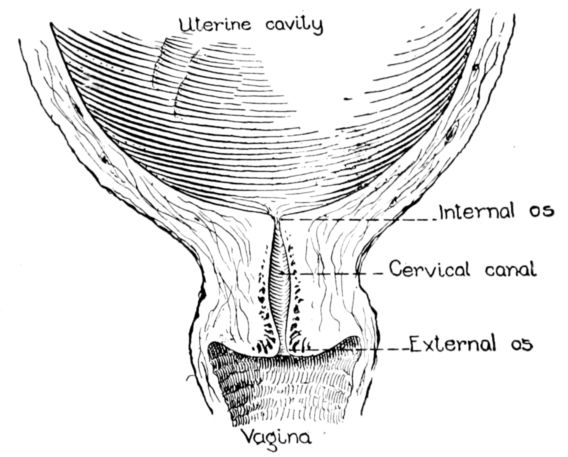

| xxi63, 64, 65, 66. | Diagrams showing stages of dilatation and obliteration of cervix | 234 |

The uterus as a whole is comprised of three parts: the fundus, that firm, rounded, head-like part above; the body, or middle portion, and the cervix, or neck, below. It is in the body and cervix that we find the long, narrow uterine cavity, divided by a constriction into two parts. The cavity of the body is little more than a vertical slit, being so flattened from before backward 33that the anterior and posterior surfaces are nearly if not quite in apposition. It is somewhat triangular in shape with an opening at each angle. (Fig. 11.) The lower of these openings leads into the cavity of the cervix through a constriction termed the internal os, while at the cornua, or two upper angles, are the openings into the Fallopian tubes.

The cavity of the cervix is spindle-shaped, being expanded between its two constricted openings, the internal os above and the external os below, which opens into the vagina. The external os in the virgin is a small round hole but has a ragged outline in women who have borne children.